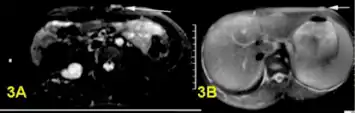

a,b)Bright plexiform neurofibroma

Histopathology of neurofibroma: A spindle cell lesion composed of slender fibroblast-like cells with storiform pattern and very low amount of stroma.[16]